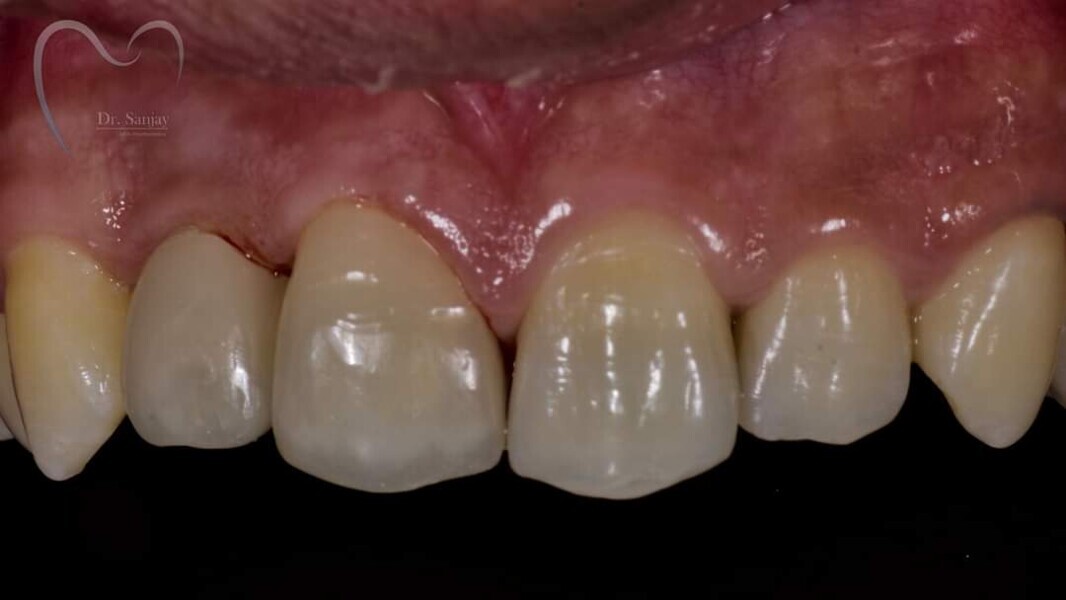

Esthetic Rehabilitation of Maxillary Anterior Teeth: Dr Sanjay Sah